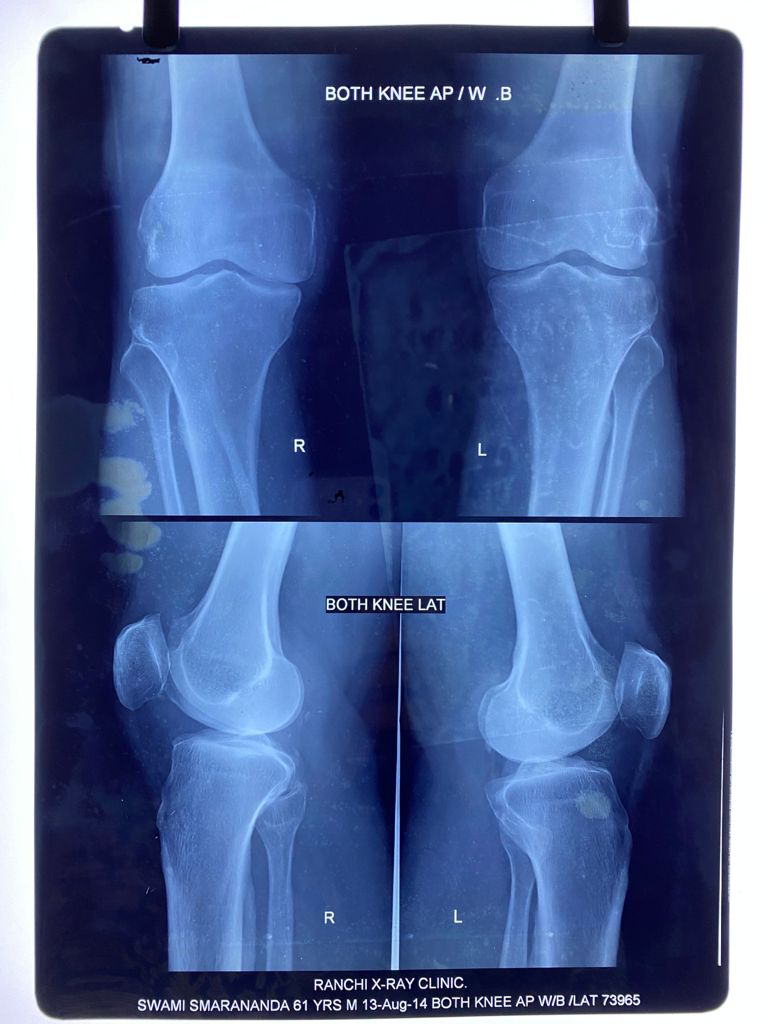

I had an episode of acute knee pain in June 2013. After studying the

X-rays and clinical examination, an Orthopaedic surgeon confirmed the onset

of osteoarthritis. He advised me to avoid climbing stairs and sitting

cross-legged. The doctor also forewarned me that I would have to undergo

knee replacement in 10 years.

August 13, 2014

August 14, 2014